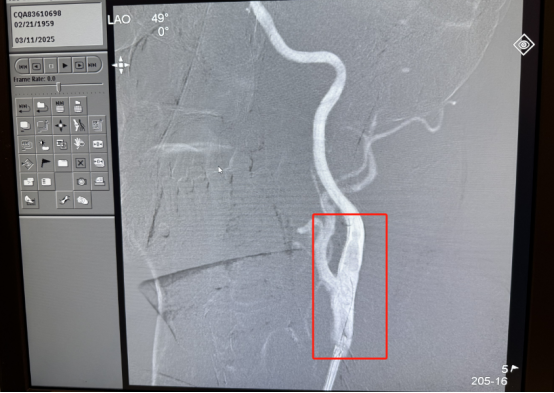

危急时刻:中风来袭,命悬一线 66 岁的解先生在毫无征兆的情况下,突然遭遇了急性卒中(脑梗塞)。他的右手臂开始发麻,尽管手有力气,但却失去了知觉;紧接着,他出现了失语,视线也变得模糊,甚至出现了重影。这些症状的背后,是颈总动脉末端形成了一个巨大的血栓,占管腔面积高达 99%!这导致了低血流动力性脑梗塞(分水岭梗塞),情况万分危急。 当解先生被紧急送往重庆莱佛士医院时,中风的时间窗已经过去,这意味着常规的溶栓治疗已经无法实施,而手术风险又极高。一旦血栓脱落,解先生将面临完全偏瘫,甚至死亡的灾难性后果。这不仅是对患者生命的巨大威胁,也给整个家庭带来了沉重的阴影。 精准施救:微创介入,妙手回春 面对如此棘手的病情,迟教授团队迅速展开深入研究和讨论。凭借丰富的临床经验和精湛的专业技术,他们决定为解先生实施血栓抽吸及颈动脉支架植入手术。这种手术方式创伤小、精准度高,但同时也对医生的技术和经验提出了极高的要求。 迟教授带领团队凭借着惊险且精湛的技术,小心翼翼地将导管插入患者体内,精准地到达血栓位置。经过一系列精细的操作,血栓被成功取出,患者的血管重新恢复了通畅,病情得到了很大缓解。